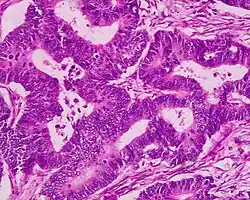

Micrograph of a villous adenoma. These polyps are considered to have a high risk of malignant transformation. H&E stain. -